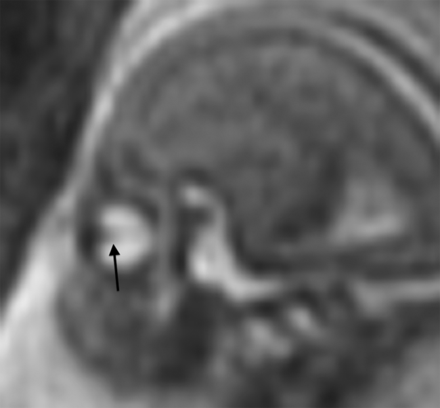

The hyaloid vasculature was visible in most patients up to 19 weeks, then occasionally up to 24 weeks (Fig 5). After that, the hyaloid vasculature system was no longer detectable.

Sagittal single-shot fast spin-echo T2WI (TR/TE, 1087/56 ms) of a normal fetal brain at 19 weeks' gestation. Linear hypointense signal extending from the posterior margin of the lens through the vitreous toward the apex represents the hyaloid vasculature (arrow).